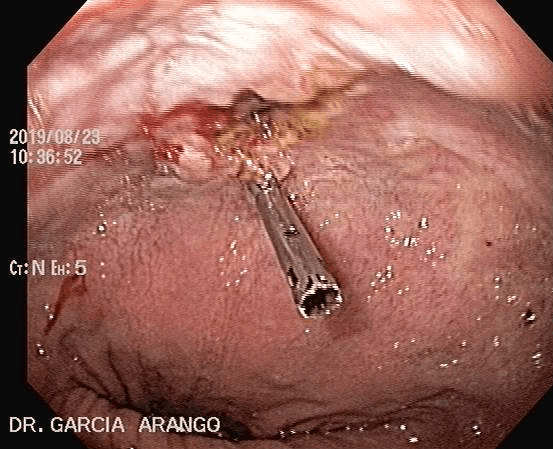

ENDOSCOPIA DIAGNÓSTICA Y TERAPÉUTICA AVANZADA CON ALTA DEFINICIÓN

⚕ Endoscopia de alta definición

⚕ Videoendoscopia y biopsias

⚕ Colocación de endoprótesis